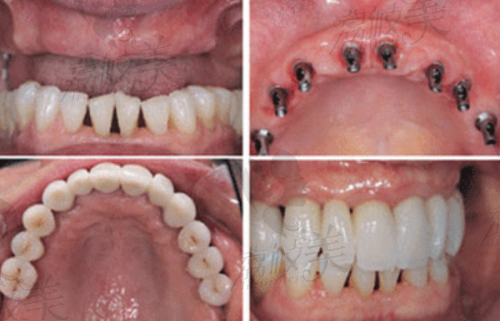

张俊伟,现任杭州中瑞联合口腔种植院长,是团队中当之无愧的“种植大师兄”。他从牙医届“资优生”一路成长为数字化种植领域的实力派代表,凭借十多年如一日的专注和磨炼,使他在全口无牙颌种植修复、骨增量重建等复杂项目中游刃有余。为数千名患者成功完成牙齿修复,不仅赢得了口腔同行的认可,也斩获了一票忠实粉丝,连“怕医生”的奶奶都愿意坐上他的椅子,安心喝茶聊天式种牙。

—— 全口/半口无牙颌方案:面对骨量不足患者,他可以灵活制定方案,实现稳固自然修复。

—— 数字化美学修复与咬合重建:让人工牙“不落俗套”,功能与美观两全齐美。

如果你还在犹豫“到底该不该种牙”,或者担心“种牙靠不靠谱”,那不妨听听张医生患者们的“亲牙体验”:种植当天能吃流食、一周后就啃鸡腿不是梦;无牙颌老人重拾咀嚼力,形象焕然一新,更有患者表示“像是换了一张脸”。这些反馈,或许正是他专精实力的至佳注脚。